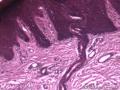

女,28岁。下肢肿物,送检带皮肤,表皮淡黑褐色,未见溃疡,

多是角质层和表皮,图11的基底层似乎有交界痣细胞?真皮太少,不好判断,是取材不好?深切一下?否则也就是描述一下了。

楼主更多图片放在角质层了,应该最主要的病变在表真皮交界的地方,不是大体是否高出皮面,如果仅是色素性斑片,表皮突延长,基底部黑素细胞增多,可以符合雀斑样痣的!